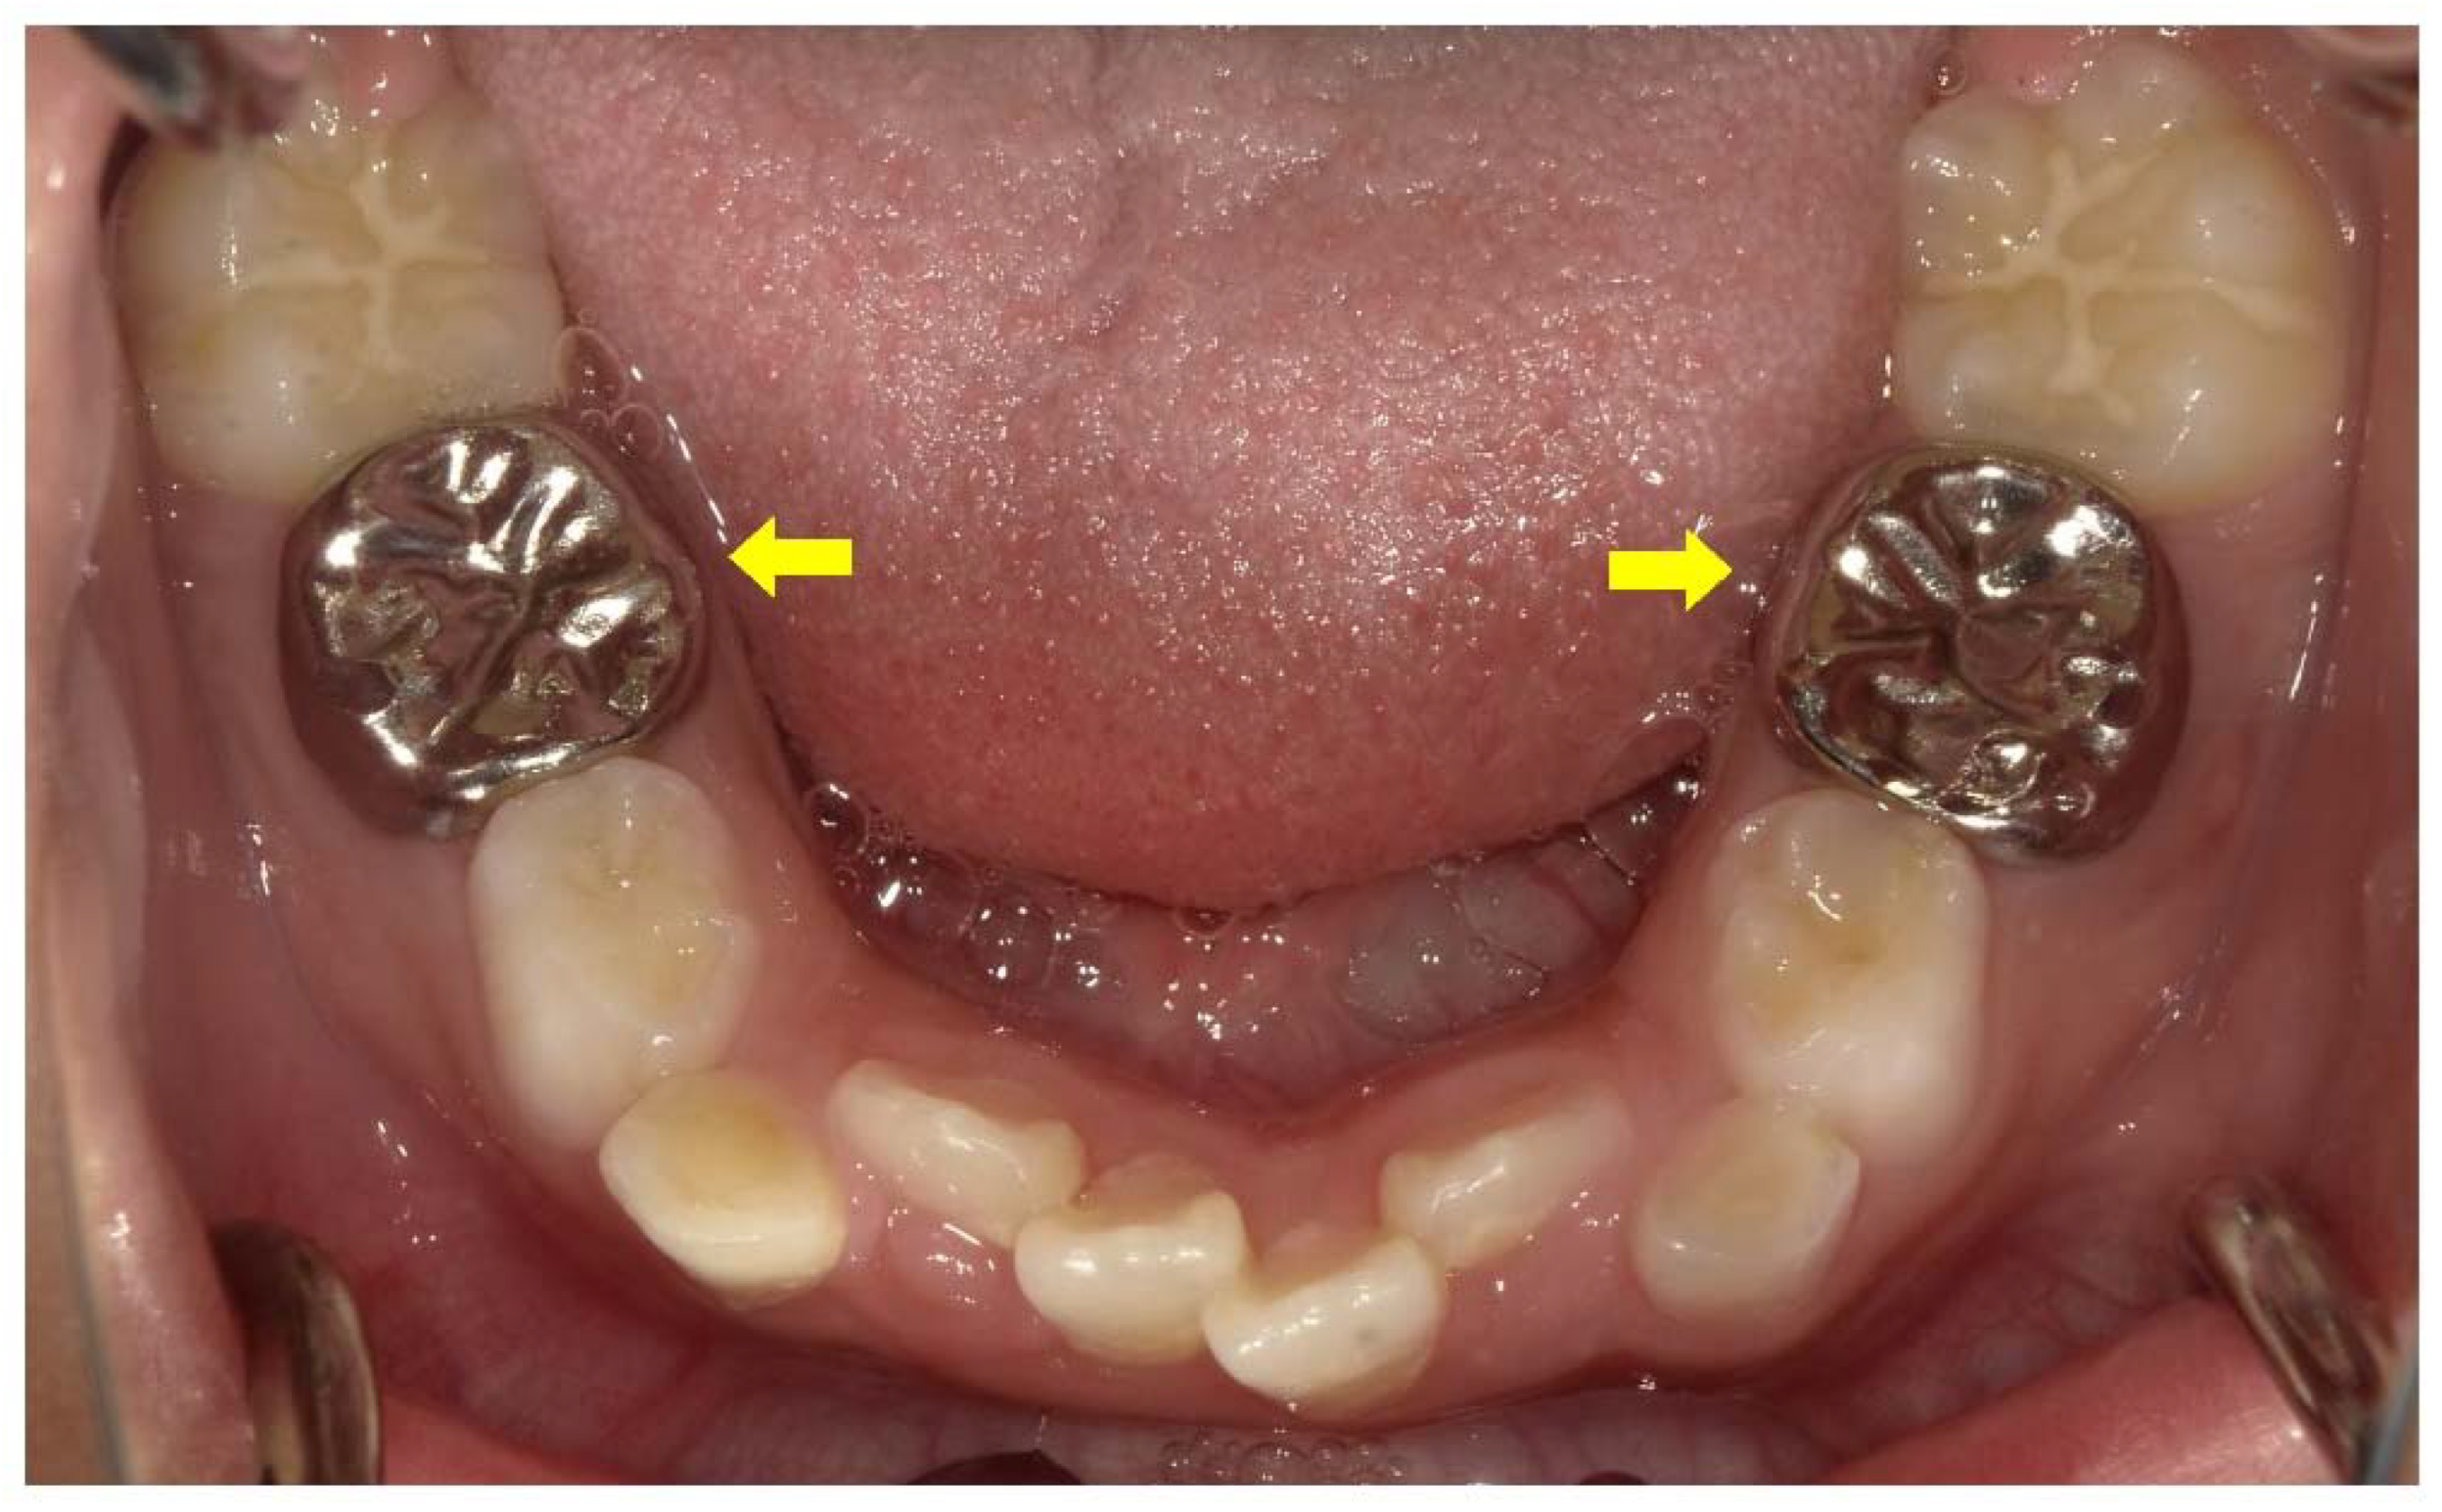

Figure 5.

Intraoral photograph of the mandibular arch of a male X-linked hypophosphatemia (XLH) patient aged 3 years 3 months. The pink color of the pulp can be seen through the enamel on the lingual side of the primary mandibular incisors (arrows).